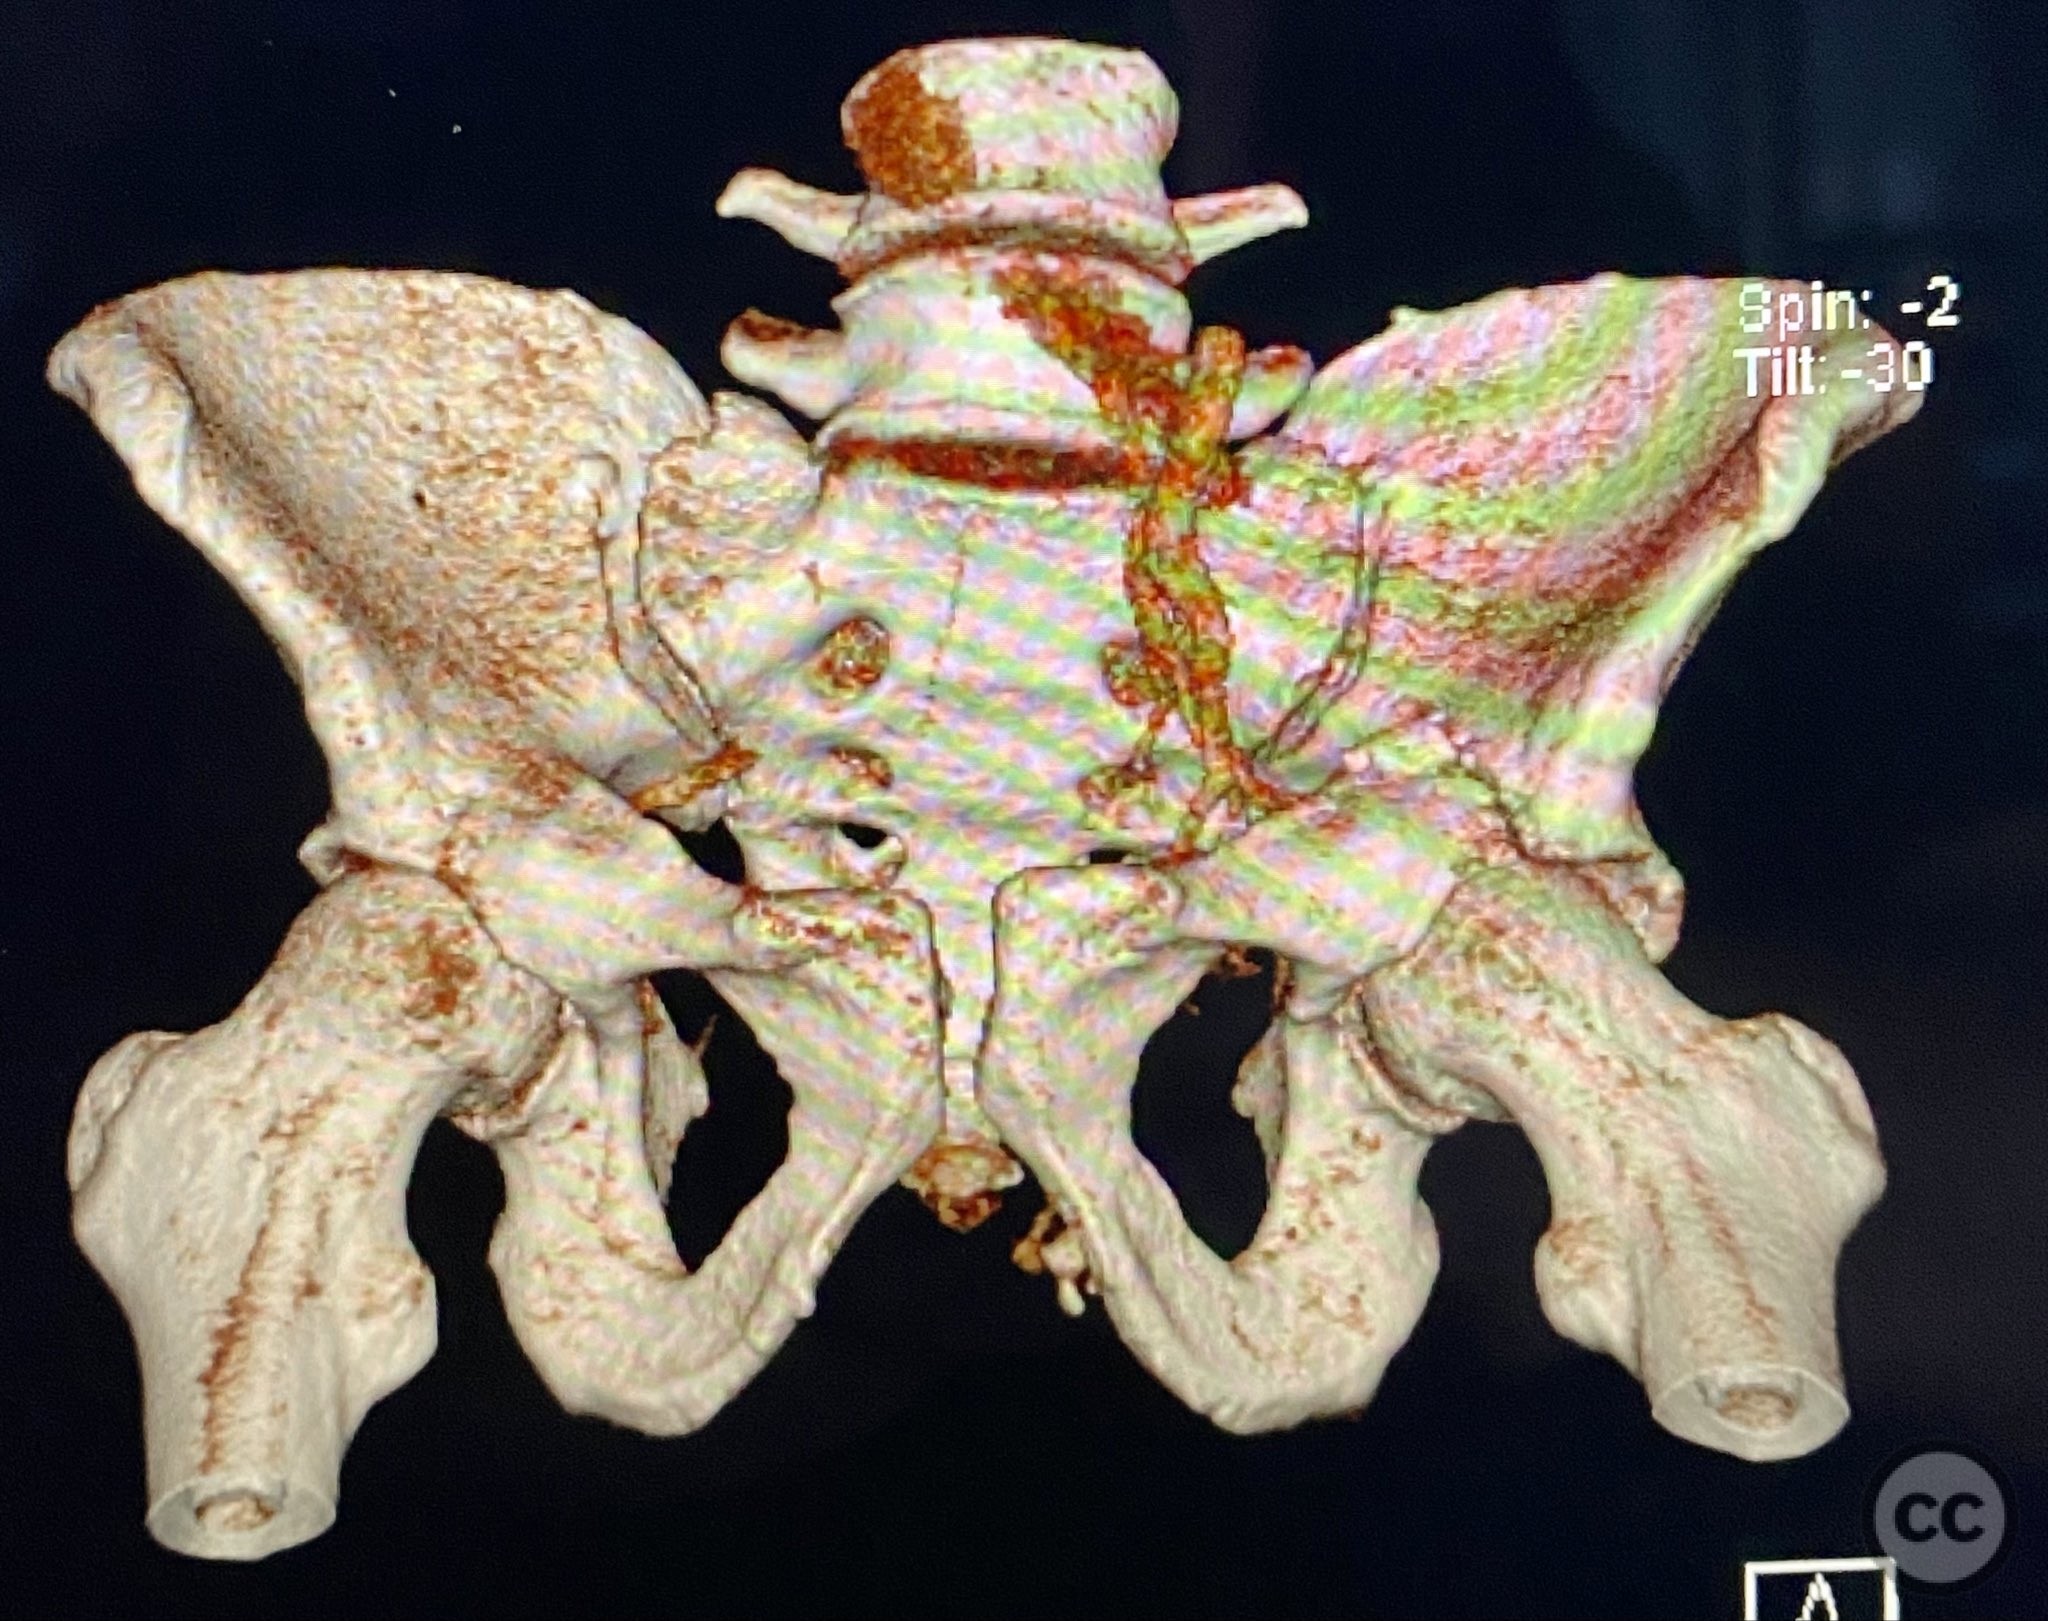

Clinical and radiological findings:  Adult male with a closed, comminuted left femoral shaft fracture and complex pelvic ring injury. Initial imaging demonstrated bilateral sacroiliac (SI) joint disruptions and a left-sided transtectal transverse acetabular fracture (Letournel-Judet: transverse type), with the fracture line exiting through the posterior wall region but without a discrete posterior wall fragment. The femoral head was displaced caudally, following the unstable distal acetabular segment, resulting in loss of congruency with the intact acetabular dome. There was also a symphyseal disruption. No associated abdominal, visceral, thoracic, cranial, or other injuries were present. Application of a circumferential pelvic binder resulted in visible changes in pelvic alignment on imaging. AO/OTA Classification: - Pelvic ring: 61-C1.3 (bilateral SI joint disruption, complete instability) - Acetabulum: 62-B1 (transverse fracture) - Femur: 32-C3 (comminuted diaphyseal fracture)